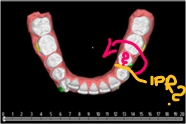

Wykonano ewaluację zaproponowanych sekwencji ruchów zębowych w dostarczonym planie 3D jednej z polskich firm nakładkowych. Opisano jak kształt i wielkość przemieszczanych zębów może wpłynąć na skuteczność kliniczną zaplanowanego leczenia.

- Zmienić typ ruchu d.13 (z derotacji wokół długiej osi na ruch wahadłowy)

- Wdrożyć IPR przy d.13

- Zmienić sekwencję ruchów zębów d.43, 44, 45 (najpierw zdystalizować 45,44 by następnie derotować 43)

- Wziąć pod uwagę inną opcję na derotację d.35 ( w pierwotnej wersji brakuje należytej przestrzeni do tego ruchu).